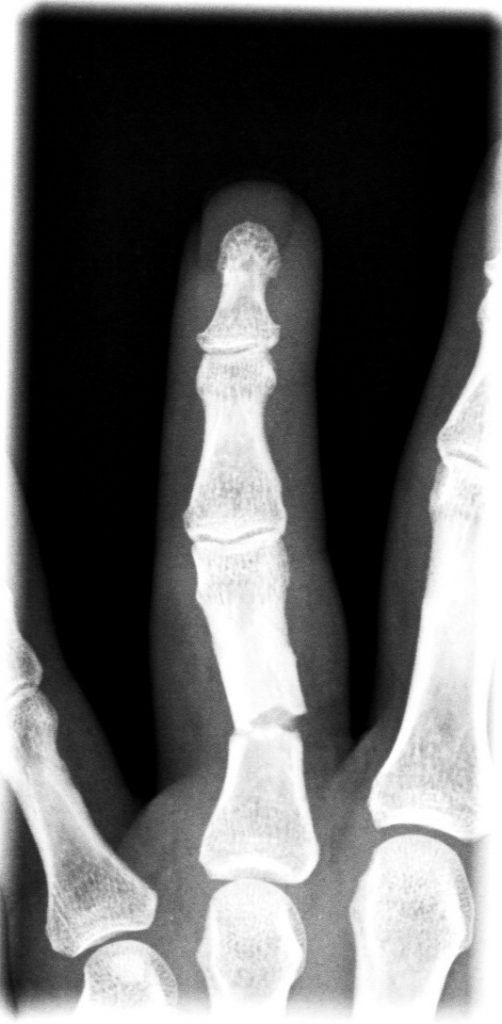

Figura 3 - Fractura conminuta falange proximal 3º dedo. (Ver también Figura 7).

Algunas fracturas se producen en la diáfisis (el tronco) del hueso, mientras que otras afectan a la articulación (intra-articulares). Las fracturas conminutas (cuando el hueso se fractura en múltiples fragmentos) por lo general se producen por traumatismos de alta energía y suelen ser inestables.

Figura 7 - Osteosíntesis con placa y tornillos de falange proximal 3º dedo.